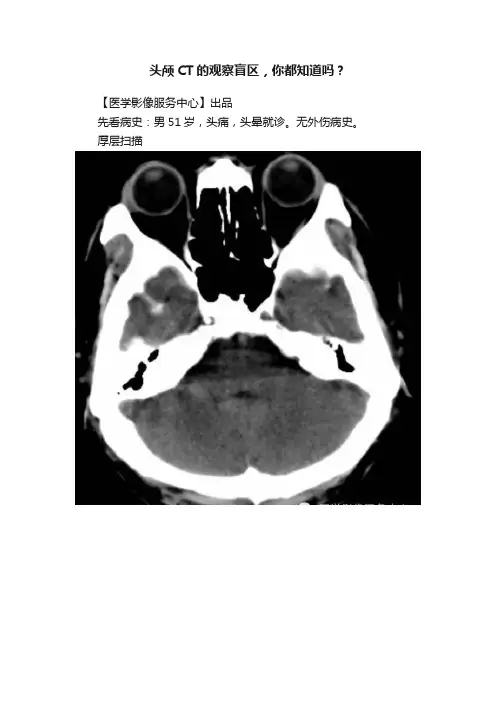

头颅CT的观察盲区,你都知道吗?【医学影像服务中心】出品先看病史:男51岁,头痛,头晕就诊。

无外伤病史。

厚层扫描CT平扫当时是9mm的图像。

后来怀疑左侧某部位有问题,就重建了1.5mm,果然!!薄层扫描点评影像,不能放过任何一个可疑的地方。

薄层,会给我们规避不少风险,带来更多信息。